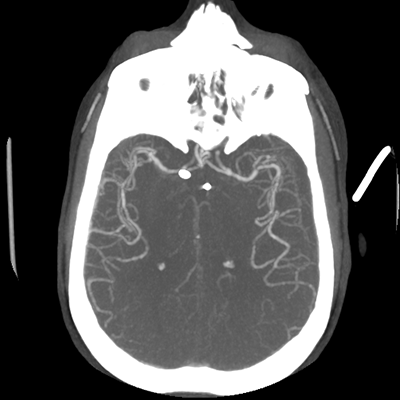

CTA head (MIP)

Starting with the non-contrast head CT, we can appreciate that there's actually not much residual subarachnoid blood at all; it's essentially all resorbed already (and cleared through the EVD). The ventricular caliber is stable. With the CTA head (for convenience's sake, the MIPs were shown), it's subtle, but we can see that the PCAs on each side are not as smooth and regular. The right MCA, starting at the bifurcation, also becomes narrower. This is [radiographic] vasospasm. Now, looking at the CT perfusion-- specifically, the Tmax (MTT) map that were selected-- there's clearly some abnormality within the bilateral cerebellar hemispheres and occipital lobes. Not a lot, but it's there. Delving further into this map, we can appreciate that the areas of abnormality are mainly green, signifying that these areas have Tmax > 6 seconds. This is the threshold that is specific, not sensitive, for vasospasm.

Putting this all together, we have thus identified radiographic vasospasm with the vessel imaging, with perfusion abnormalities that are concordant with it. Does the area of vasospasm and hypoperfusion correlate with the patient's clinical exam?